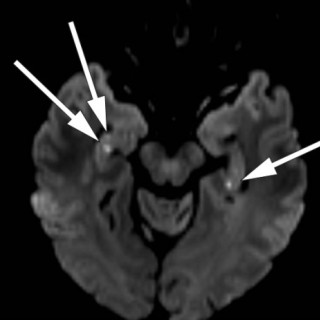

En mann i 70-årene ble henvist hematologisk poliklinikk grunnet redusert allmenntilstand og anemi. Blodprøver viste hemoglobin 9,7 g/dl (13,4–17,0), gjennomsnittlig cellevolum i de røde blodcellene (MCV) 115 fl (82–98), leukocytter 3,0 · 10 9/l (3,5–11,0), trombocytter 187 · 10 9/l (145–348), folat 7,2 nmol/l (> 8,0), kobalamin 693 pmol/l (175–700) og ferritin 831 µg/l (34–300). Tilstanden ble oppfattet som megaloblastisk anemi på grunn av folatmangel, og man startet med folatbehandling. Kontroll etter to måneder viste vedvarende anemi med hemoglobin 9,4 g/dl. Benmargsutstryk med May-Grünwald...